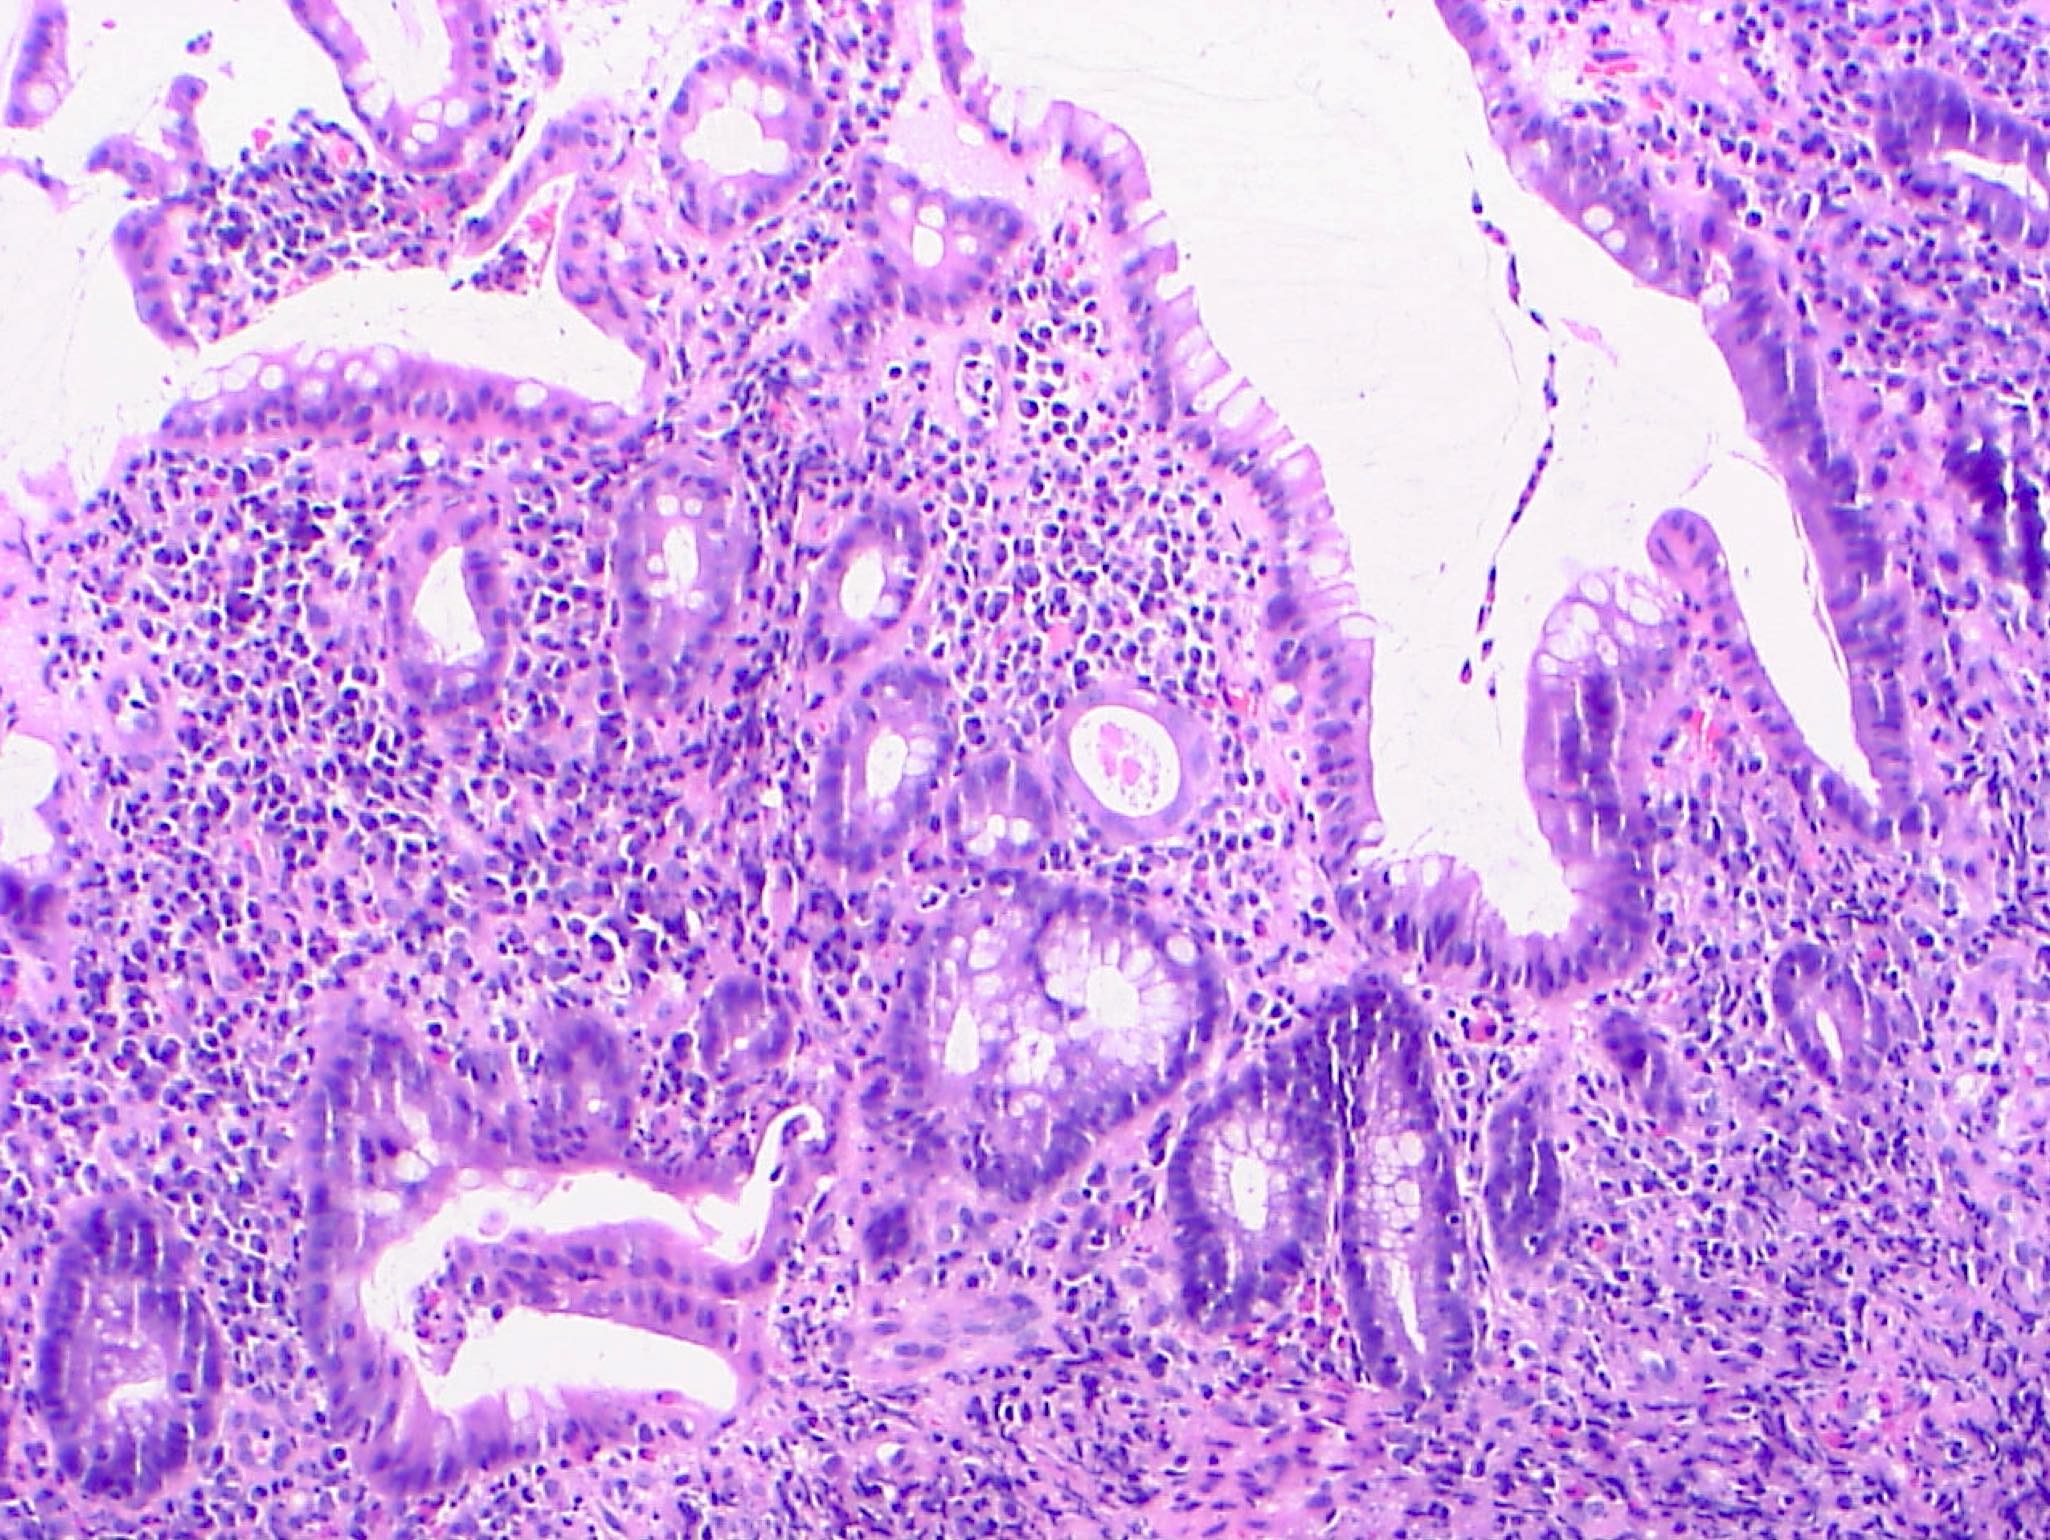

Microscopic (histologic) description

- Low grade dysplasia:

- Preserved nuclear polarity

- Pseudostratified, crowded, elongated and hyperchromatic nuclei

- Lack of surface maturation, i.e. abnormalities persist to surface

- High grade dysplasia:

- May show complex architecture, such as cribriform glands

- Loss of nuclear polarity

- Nuclear pleomorphism, vesicular nuclei and prominent nucleoli

- Indefinite for dysplasia:

- Reserved for cases when distinction between dysplasia and reactive epithelial atypia cannot be made

- Mucosal erosion or ulceration (precluding assessment of surface maturation) or prominent inflammation may be sources of difficulty

Microscopic (histologic) images